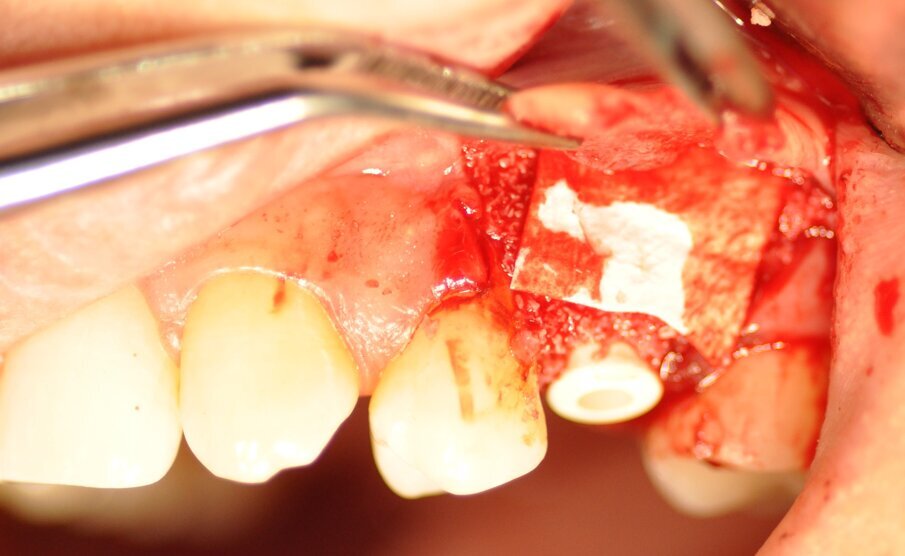

La paziente presentava un primo premolare superiore sinistro non recuperabile. La CBCT mostra la situazione iniziale (Fig. 1). Si noti quella che appare come una grande fenestrazione buccale nell’area della resezione radicolare (Fig. 2). Il dente fratturato è stato estratto (Figg. 3, 4). Lo scollamento del lembo di accesso rivela la fenestrazione buccale (Fig. 5). L’osteotomia è stata preparata secondo il protocollo di fresatura di Neoss ProActive Edge (Fig. 6). Successivamente viene posizionato un impianto Neoss ProActive Edge Ø 5.0 × 13 mm (Fig. 7). L’impianto è stato posizionato in una situazione di disponibilità ossea molto limitata e densità ossea media (Fig. 8). Nonostante le limitazioni dovute alla condizione ossea, è stata raggiunta una buona stabilità primaria. È stato utilizzato un torque di inserimento di 20 Ncm, l’ISQ è risultato in un range di 70/77. Per correggere la fenestrazione buccale è stato eseguito un innesto con particolato osseo di origine porcina (Fig. 9). L’innesto osseo è stato coperto con una membrana di collagene riassorbibile (Fig. 10). Il lembo mucoso è stato suturato attorno al pilastro di guarigione in PEEK, consentendo la guarigione in una sola fase (Fig. 11).